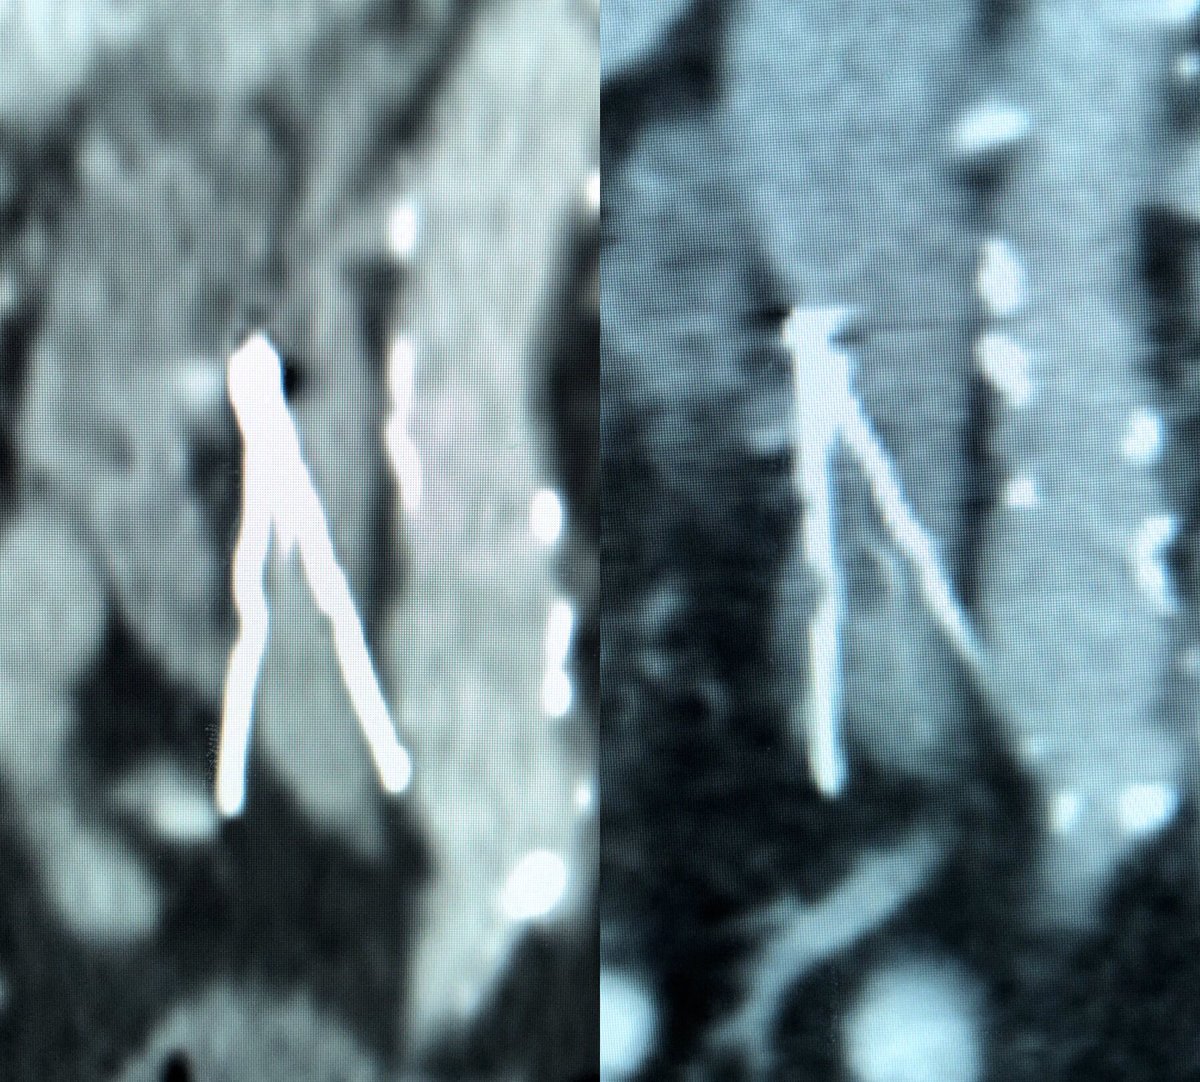

IVC filter doing its job! Clot trapped in filter (right) not seen 3 weeks before (left).

#IRad#TwittIR#Radiologypic.twitter.com/UjYIBtIUFp